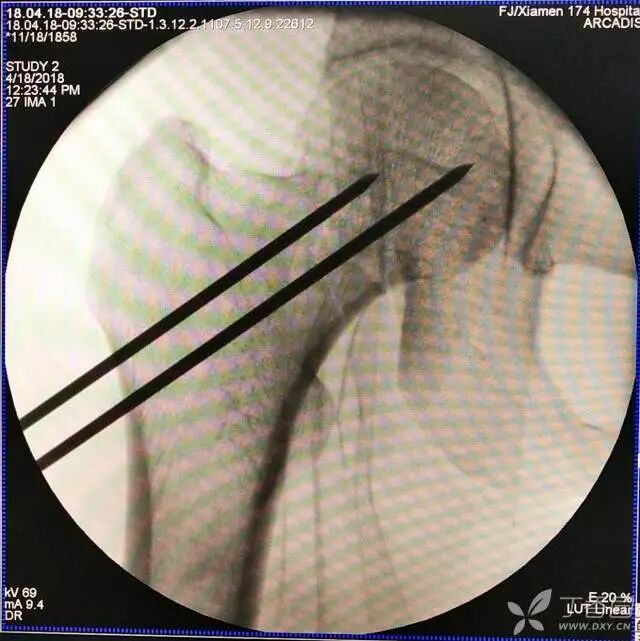

5. 打入第一枚倒品字下方导针,跟体外导针基本重叠

牵引床怎么用视频详解:如何不使用牵引床做好一台股骨颈骨折?_https://www.jmylbn.com_新闻资讯_第13张